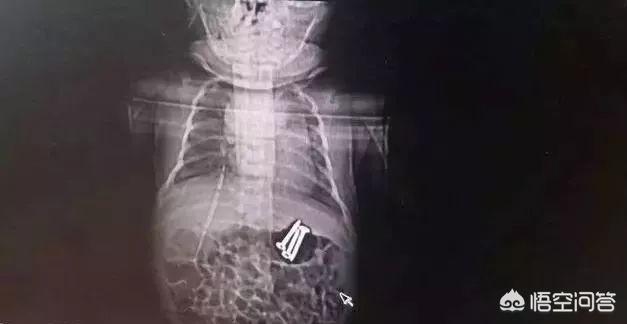

6月5日21:00左右,一条微信在河南医务人员朋友圈热传:“杀手”无处不在,危险此起彼伏。二孩时代,熊孩子无所不能,这个3岁哥哥喂给37天弟弟的三枚3.5厘米的螺丝钉,经我们消化科同仁成功取出。

看了这,真是替那个小宝捏把汗,得亏最后通过胃镜把三枚钉子取出来了,钉子也没伤到孩子的食管。真是不幸中的万幸啊!有惊无险。